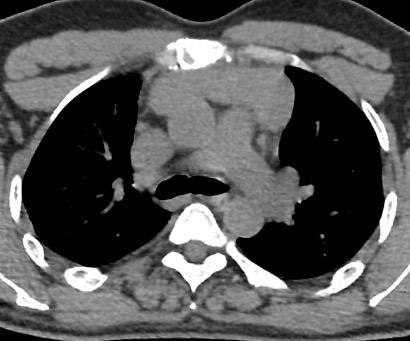

Formez-vous au dépistage Des places sont encore disponibles pour la formation au dépistage du cancer du poumon par scanner basse dose

Projet IMPULSION Le projet IMPULSION a été sélectionné en janvier 2025 comme programme pilote du dépistage du cancer du poumon par scanner